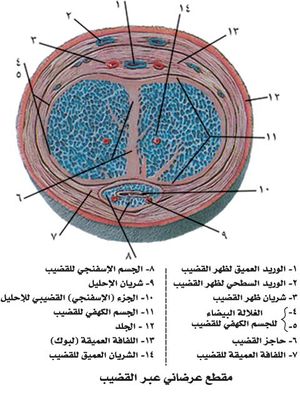

القضيب

وهو عضو الجماع والتبويل يتألف من الجسمين الكهفيين corporea cavernosa المشكلين من أسطوانتين إسفنجيتين في الظهر والجانبين ومن الجسم الإسفنجي spongiosum corpus في بطن القضيب، يمر فيه الإحليل الذي ينقل البول والسائل المنوي، ويبدأ بتوسع بصلي الشكل في العجان، وينتهي في ذروة القضيب بكتلة مخروطية الشكل تسمى الحشفة glans التي تغطيها القلفة prepuce.

فيزيولوجية القضيب

للقضيب وظيفتان الأولى: نقل البول والمني للوسط الخارجي بوساطة الإحليل، والثانية: هي الوظيفة الجنسية المتمثلة بالانتصاب أو النعوظ. وإن آلية الانتصاب معقدة نوعاً ما، ويدخل فيها عناصر عدة، ويمكن تبسيطها بما يأتي:

تتم عملية الانتصاب بتمدد شديد للجسمين الكهفيين وتوترهما من جراء احتقان الدم فيهما بحيث يكون مقدار الوارد الدموي للجسمين عالياً خاصة في مرحلة بدء الانتصاب. وكلما ازداد امتلاء الجسمين الكهفيين وتوترت المحفظة الليفية المحيطة بهما خمصت الأوردة التي تحمل الدم الصادر من الجسمين الكهفيين، وتعيق خروجه مدة قصيرة هي مدة دوام الانتصاب. ومما يحافظ على دوام الانتصاب أثناء الجماع تقلص العضلات الوركية الكهفية والوركية الإسفنجية بآلية عصبية انعكاسية نتيجة تنبه القضيب الآلي في أثناء الجماع.

أما بعد القذف فيحدث تنبيه ودي يؤدي إلى تقلص الشرايين الواردة للقضيب من جهة، كما أن المواد المفرزة من النهايات العصبية والمؤدية لاسترخاء عضلات كُهيفات الجسم الكهفي تستنفذ، وكلتا الآليتين تؤدي لتقلص هذه العضلات مفرغة الدم من الكُهيفات ومنقصة التوتر ضمن الجسم الكهفي مما يؤدي إلى انفتاح طرق العود الوريدي للجسم الكهفي التي كانت مضغوطة في مرحلة الانتصاب، ومن ثم عودة الدم إلى الأوردة القضيبية الراجعة وزوال الانتصاب.

آفات القضيب

يتألف القضيب من الجسمين الكهفيين وقناة الإحليل المحاطة بالجسم الإسفنجي الذي يتضخم في مقدمة القضيب ليشكل الحشفة ومن غلف صفاقية وضامة وجلدية. يمتد الغلاف الجلدي في مقدمة القضيب ليشكل القلفة التي تحيط بالحشفة.

آفات الأجسام الناعظة

هذه الأجسام هي الجسمان الكهفيان والجسم الإسفنجي وتتعرض لآفات كثيرة منها: